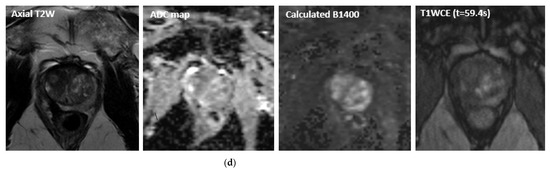

- Ghai, S.; Louis, A.S.; Van Vliet, M.; Lindner, U.; Haider, M.A.; Hlasny, E.; Spensieri, P.; Van Der Kwast, T.H.; McCluskey, S.A.; Kucharczyk, W.; et al. Real-Time MRI-Guided Focused Ultrasound for Focal Therapy of Locally Confined Low-Risk Prostate Cancer: Feasibility and Preliminary Outcomes. Am. J. Roentgenol. 2015, 205, W177–W184. [Google Scholar] [CrossRef]

- Ghai, S.; Perlis, N.; Lindner, U.; Hlasny, E.; Haider, M.A.; Finelli, A.; Zlotta, A.R.; Kulkarni, G.S.; Van Der Kwast, T.H.; McCluskey, S.A.; et al. Magnetic resonance guided focused high frequency ultrasound ablation for focal therapy in prostate cancer–phase 1 trial. Eur. Radiol. 2018, 28, 4281–4287. [Google Scholar] [CrossRef]

- Ghai, S.; Finelli, A.; Corr, K.; Chan, R.; Jokhu, S.; Li, X.; McCluskey, S.; Konukhova, A.; Hlasny, E.; van der Kwast, T.H.; et al. MRI-guided Focused Ultrasound Ablation for Localized Intermediate-Risk Prostate Cancer: Early Results of a Phase II Trial. Radiology 2021, 298, 695–703. [Google Scholar] [CrossRef]